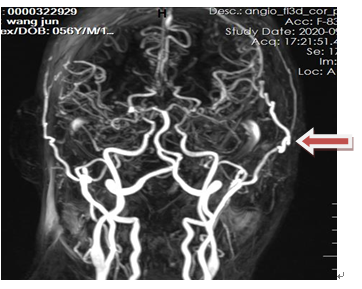

DSA:顱底煙霧狀血管形成(箭頭所示)。